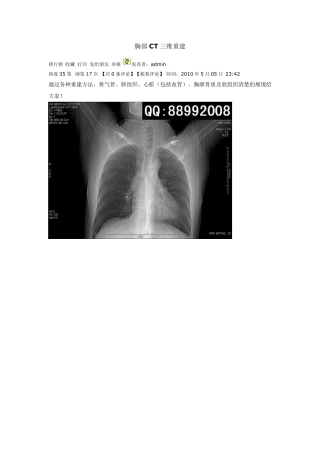

胸部CT 三维重建 排行榜 收藏 打印 发给朋友 举报 发布者:admin 热度35 票 浏览17 次 【共0 条评论】【我要评论】 时间:20...